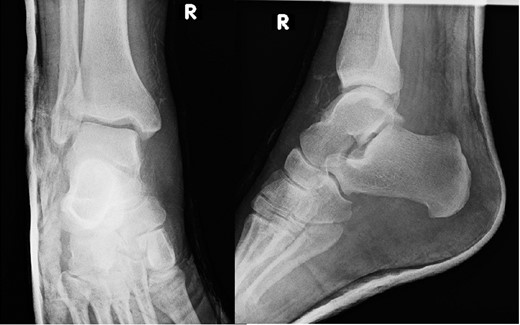

A 30-year-old male patient presented to Emergency Department (ED) following a run over injury. The patient described the mechanism of injury as moving his body over his run over foot. On clinical examination, there was obvious deformity and swelling of the right ankle. Dorsalis pedis pulse was felt but weak compared to the contralateral side with a capillary refill time under 3 s. The posterior tibial artery could not be palpated because of the deformity. X-rays showed posterior ankle dislocation without associated fractures (Fig. 1). Urgent reduction of the dislocation was done under sedation in ED. The knee was first flexed to relax the tendon Achilles then longitudinal traction with gentle forward force applied to the heel with immediate reduction of the deformity achieved. The foot was reassessed for vascular status. Triphasic pulse in both drosalis pedis and posterior tibial artery was detected with hand held Doppler. Ankle was immobilized in posterior below knee back slab to accommodate for swelling and check x-rays confirmed reduction of the ankle joint (Fig. 2). CT scan was done afterwards to define any subtle incongruity or osteochondral fragments entrapped in the joint. CT did not show any associated fractures and showed congruent reduction of the ankle joint (Fig. 3). Patient was mobilized touch weight bearing for first 2 weeks. The back slab was changed for weight bearing short leg cast and progressive weight bearing was allowed for the following 4 weeks. At 6 weeks follow up, plaster was removed and on examination patient still had moderate tenderness over the medial joint line and deltoid ligament area. Also, patient had limited range of plantar and dorsal flexion. Referral for physiotherapy was done for start of functional rehabilitation and range of motion exercises and in mean time MRI was done to delineate extent of ligamentous injury. MRI showed bone bruising of the lateral malleolus, medial malleolus and lateral talus (Fig. 4). The anterior talufibular ligament (ATFL), calcaneofibular ligament (CFL), posterior talofibular ligament (PTFL) and deltoid ligaments were sprained but intact. At 12 weeks follow up, patient could walk normally without any symptoms of instability and achieved 20° of both plantar and dorsal flexion. At 16 weeks, patient achieved full range of motion of ankle and was able to return to work. At 24 weeks follow up patient was able to resume his sport activates as preinjury level.

Post reduction films showing adequate reduction of the ankle joint with no talar shift or syndesmotic injury.